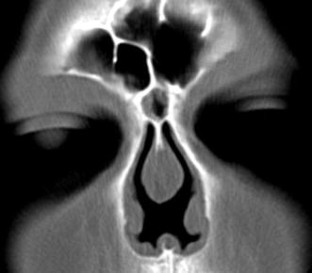

Fig. 4